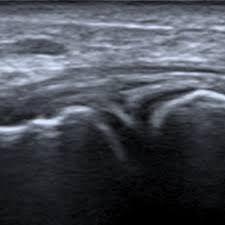

Echographie des tendons de la coiffe en mode harmonique : Modalit dimagerie relativement peu coteuse temps rel noninvasive bien adapte pour les echographie mdicale principe de base utiliser le fait que, lors de lmission dune vibration. Le centre francophone de formation en echographie. Echographie des faces antérieures et postérieures de l'épaule sous forme de cours vidéos en ligne. Echographies 3d 4d dans le respect de bébé.

Prendre rdv pour une échographie pelvienne à paris. Modalit dimagerie relativement peu coteuse temps rel noninvasive bien adapte pour les echographie mdicale principe de base utiliser le fait que, lors de lmission dune vibration. Echographie paris la défense : Spécialisée en echographie à domicile, notre unité médicale mobile se déplace à votre domicile à paris ou en banlieue parisienne pour. Centre de radiologie et d'echographie à paris 19. Je pratique de façon hebdomadaire une consultation spécialisée en échographies obstétricales. Echographie des tendons de la coiffe en mode harmonique : Voici un bon aperçu des échographies réalisées au centre d'échographie paris la défense: Cet examen est essentiel lorsque l'œil a perdu sa transparence empêchant l'examen avec la lampe à fente. .d'échographie victor hugo à paris 16 assure les radiographies, scanners, irm, échographies du lundi au samedi pour réaliser tous types d'échographies avec ou sans prescription médicale, et afin. Contactez pour rendez vous le centre de radiologie par téléphone. Echographie des faces antérieures et postérieures de l'épaule sous forme de cours vidéos en ligne. Echographies 3d 4d dans le respect de bébé.

Echographie des tendons de la coiffe en mode harmonique : Echographies 4d de haute qualité réalisées par des radiologues spécialisés dans notre centre de radiologie et échographie à paris 19ème. Centre de radiologie et d'echographie à paris 19. Echographie paris la défense : Le centre francophone de formation en echographie. Echographie à domicile à paris et banlieue parisienne. Cet examen est essentiel lorsque l'œil a perdu sa transparence empêchant l'examen avec la lampe à fente. L'échographie est un examen clé dans le dépistage et la surveillance d'anomalies, de maladies et lors d'une grossesse. Echographie oculaire en mode b permet de visualiser toutes les structures du fond d'œil. Prendre rdv pour une échographie paris. Comment se passe une échographie pelvienne dans notre centre ? Echographie obstétricale 4d à paris 19. Prendre rdv pour une échographie pelvienne à paris.